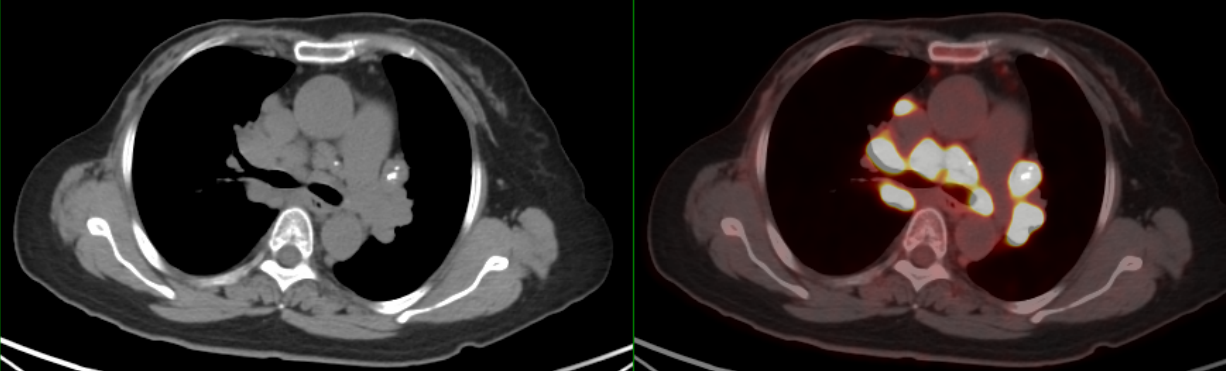

PET/CT示:雙側(cè)鎖骨上、縱隔、胸骨后、雙肺門(mén)、雙側(cè)肋骨旁、腹腔、腹膜后、盆腔及左側(cè)腹股溝見(jiàn)多枚代謝異常增高淋巴結(jié),較大者約3.4×2.1cm,SUVmax約20.7。

PET/CT診斷:考慮結(jié)節(jié)病,建議病理檢查。

患者8個(gè)月后復(fù)查胸部CT示:縱隔、雙肺門(mén)淋巴結(jié)較前明顯縮小,較大者約1.4×1.1cm。

此例患者由于乳腺癌的病史,臨床初步懷疑轉(zhuǎn)移。PET/CT顯示縱隔、肺門(mén)淋巴結(jié)腫大,且呈對(duì)稱(chēng)性分布,密度均勻,邊界清晰,無(wú)明顯融合,F(xiàn)DG高攝??;此外可見(jiàn)多發(fā)腹盆部,頸部淋巴結(jié)次之,分布較散,體積及FDG攝取小于縱隔和肺門(mén)淋巴結(jié),也不是乳腺癌術(shù)后易轉(zhuǎn)移的部位。綜上考慮符合結(jié)節(jié)病表現(xiàn),最終得到病理證實(shí),患者因此避免了不必要的抗腫瘤治療。